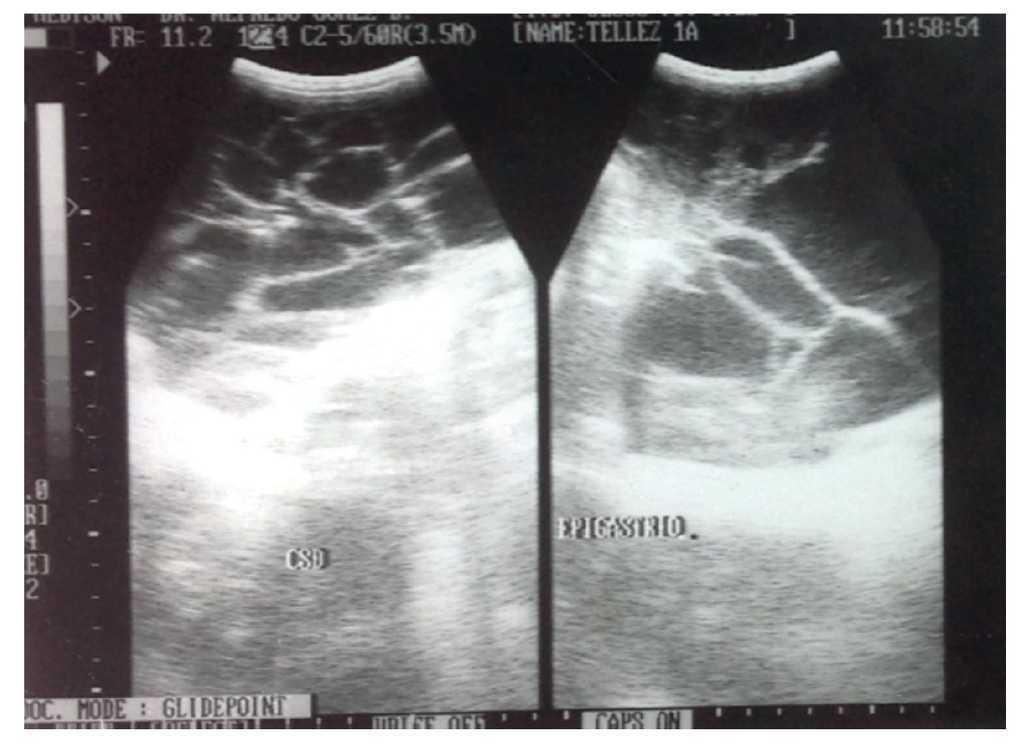

Inició su padecimiento 6 meses previos, con rechazo al alimento y distensión abdominal. Es llevado a centro de salud donde le prescriben hierro y vitaminas A, C y D. En el último mes se agregaron evacuaciones líquidas color verdoso, con moco. Se manejó con electrolitos orales, remitiendo el cuadro. Su médico de primer contacto solicitó estudios de laboratorio, los cuales registraron anemia microcítica e hipocrómica. Además, el ecosonograma abdominal mostró masa quística intra-abdominal multilobulada extendiéndose por ambas correderas y hueco pélvico. Riñones, hígado y vesícula biliar se presentaron sin alteraciones (fig. 1).

Figura 1 Se tomó estudio con equipo Medison de alta resolución, con transductor convexo. Se observó una imagen de aproximadamente 12.2 x 6.8 cm, de aspecto anecoico multitrabeculado.

Para el diagnóstico de las malformaciones linfáticas se utilizan ecografía, tomografía axial computarizada (TAC) y resonancia magnética nuclear. En este caso, con ecografía y TAC abdominal se observó una masa quística multilobulada que se extendía por ambas correderas y hueco pélvico. En la mayoría de los ecosonogramas realizados a pacientes con malformaciones linfáticas, se visualiza una masa hipoecogénica con septos en su interior. La TAC tiene la utilidad de ver la extensión y afectación de otras estructuras, valora si son tumores intraperitoneales, y ciertas características, como heterogeneidad interna, densidad grasa, formación quística y calcificaciones, lo que aporta una idea del grado de benignidad del tumor11.